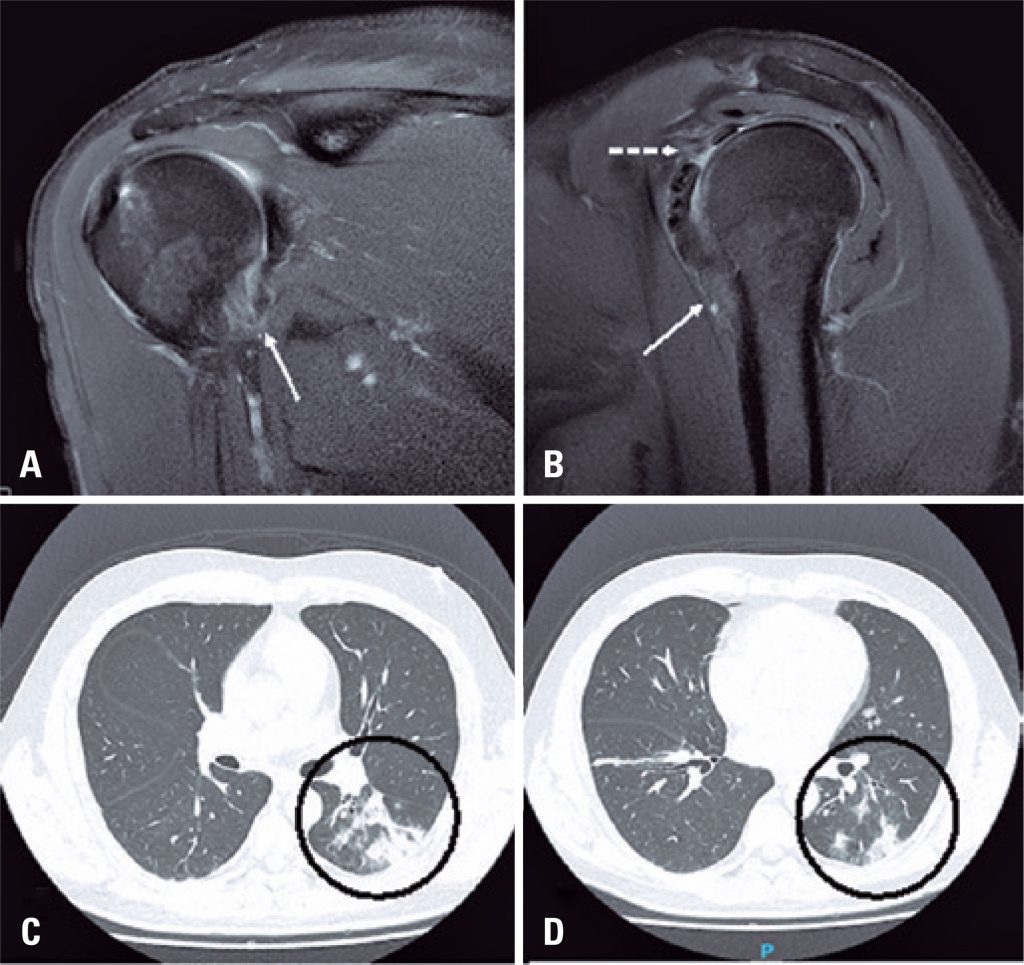

MRI Findings in Adhesive Capsulitis of the Shoulder Sports Medicine Adhesive Capsulitis Incidence 50 generally, rom loss of greater than 25% in at least 2 planes and passive external rotation loss that is greater than 50% of the uninvolved shoulder or less than 30° of. patients with adhesive capsulitis present with a number of impairments, but most characteristically have a global loss of both active and passive shoulder rom. learn about. Adhesive Capsulitis Incidence.

MRI Appearance of Adhesive Capsulitis Illinois Chiropractic Society Adhesive Capsulitis Incidence a comprehensive review of the diagnosis and management of frozen shoulder, a condition of global limitation of shoulder. patients with adhesive capsulitis present with a number of impairments, but most characteristically have a global loss of both active and passive shoulder rom. 50 generally, rom loss of greater than 25% in at least 2 planes and passive external. Adhesive Capsulitis Incidence.